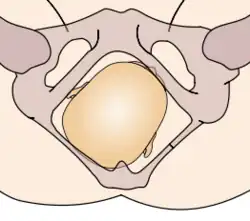

Durante la mecánica del parto, los diámetros menores del feto pasan por los diámetros mayores de la pelvis materna. Con el fin de no quedar encajado en algún punto durante su trayectoria fuera del útero, el neonato pasa por una serie de movimientos naturales que constituyen el mecanismo del parto.

- Rotación interna: ocurre en el estrecho medio de la pelvis, cuando el feto, al continuar su descenso, hace una rotación de 90° en el sentido contrario a las agujas del reloj, de modo de adaptarse a la configuración romboidal de los músculos del piso pélvico, entre el músculo elevador del ano y los ileocoxígeos. Así, la cara del bebé está dirigida mirando hacia el recto materno.

La relación de la fontanela posterior con la pelvis materna determina el diagnóstico de posición. Se distinguen ocho posiciones en la presentación de vértice: I. Occípito ilíaca izquierda anterior (OIIA) en que la fontanela posterior se ubica hacia delante en relación con la pelvis materna y además a la izquierda de la madre. La sutura sagital está orientada oblicuamente. II. Sucesivamente dependiendo de la ubicación de la fontanela posterior (porque la pelvis es siempre la misma) las posiciones serán:

- Occípito ilíaca derecha anterior OIDA

- Occípito ilíaca izquierda posterior OIIP

- Occípito ilíaca derecha posterior OIDP

- Occípito ilíaca derecha transversa OIDT

- Occípito ilíaca izquierda transversa OIIT